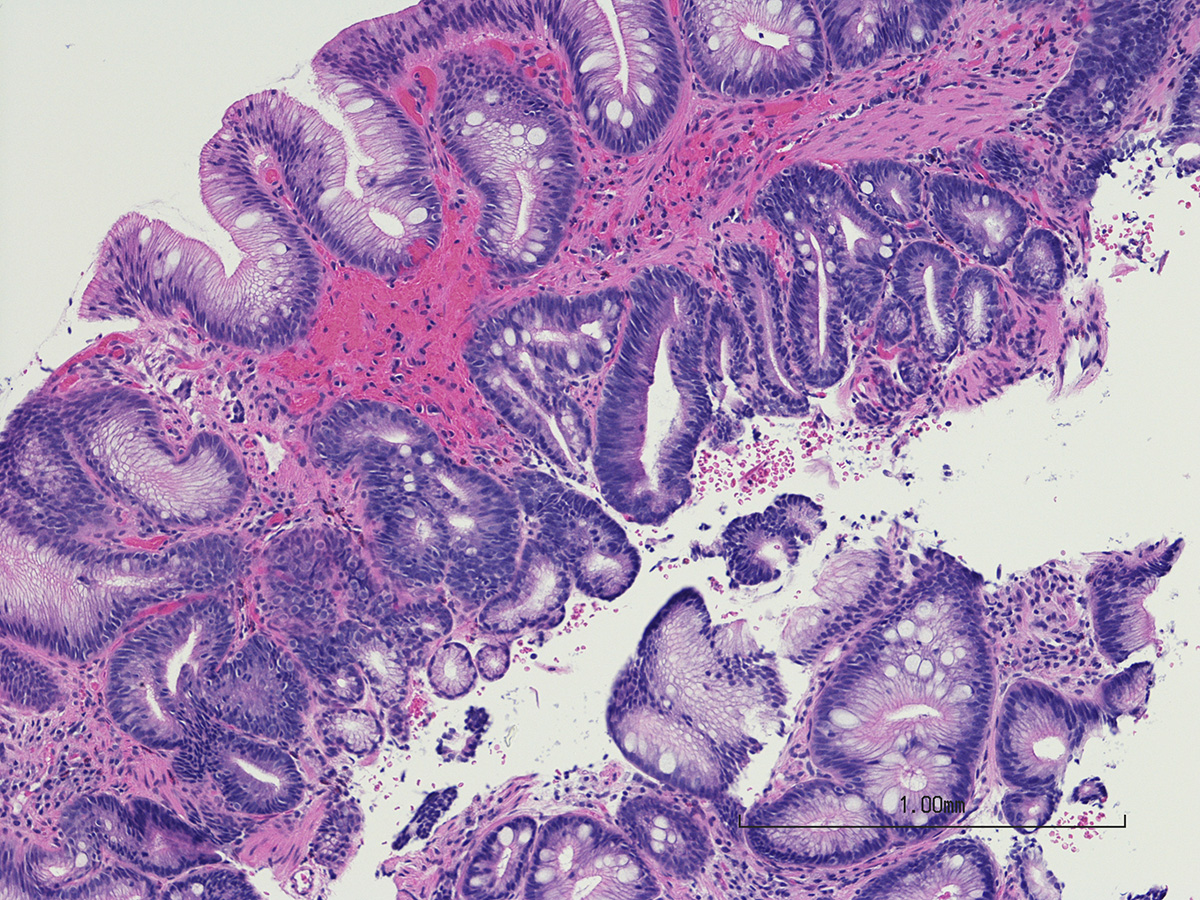

«Το Σύνδρομο Barrett (Οισοφάγος Barrett) είναι ανάπτυξη εντερικής μετάπλασης στον οισοφάγο. Πρόκειται, δηλαδή, για μια προκαρκινική αλλοίωση που εμφανίζεται στον οισοφάγο, ενώ μπορεί να εμφανιστεί και στο άνω μέρος του στομάχου», μας λέει ο κ. Οικονόμου, που διευκρινίζει ότι δεν πρόκειται για καρκίνο.